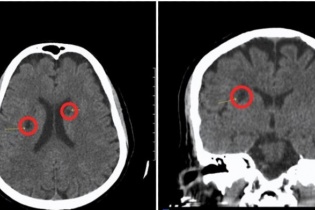

Chỉ trong vòng 30 phút từ khi nhập viện, một cụ bà 70 tuổi đã được các bác sỹ cấp cứu kịp thời bằng phương pháp tiêm thuốc tiêu sợi huyết, vượt qua cơn đột...